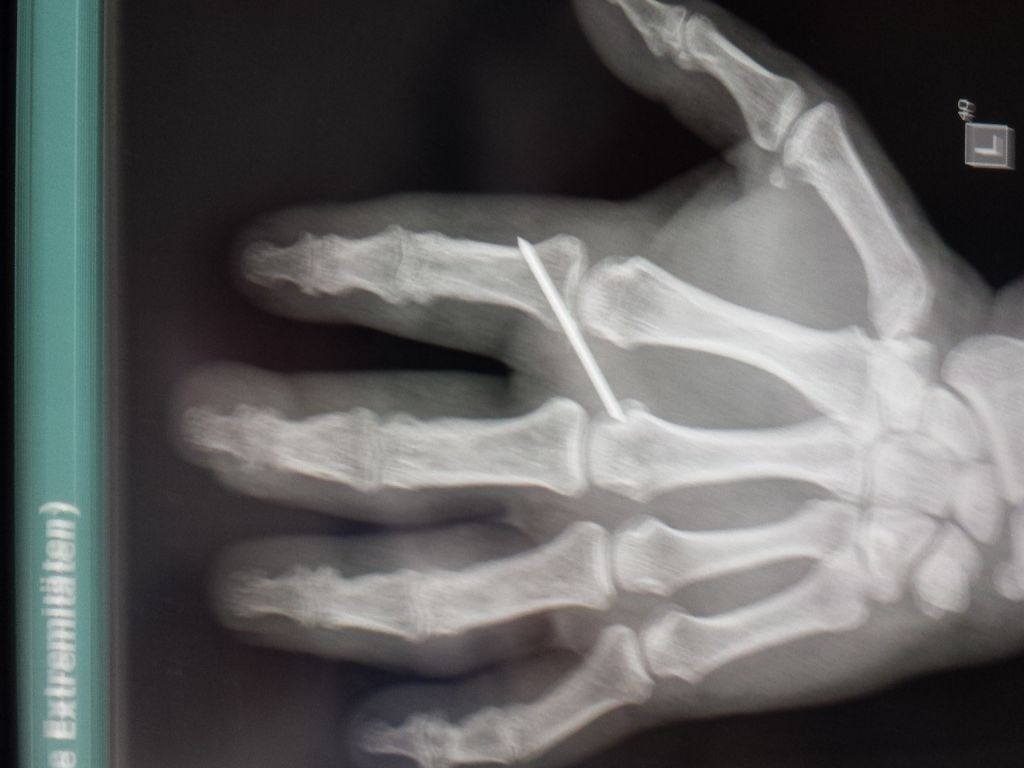

hast du eig. noch den Metallstift in deinem Finger? :wirr:

MichaelDerVierte hat geschrieben:du Siggi,

Klaro, regulär bis 20.10.2014, habe morgen einen Termin zur Besprechung im KH, um 14.15°°.

War heute beim Oberarzt zum Nachsehen, sieht suuuper aus.

Nach seinen Worten hat er nicht damit gerechnet, dass es so schnell und reibungslos verheilt.

Nach dem Röntgen meinte er, dass einer Entfernung des Nagels nichts entgegensteht.

Dann fragte er mich, wenn ich Ihn raus haben möchte, ich sagte sofort morgen!

Das geht natürlich nicht, weil die op Pläne schon feststehen, aber Montag komme ich als erster Ambulant mit örtlicher Betäubung dran.

Ist nur ein ganz kleiner Eingriff meinte er.

Ich finde das Spitze!

Habe auch direkt ein Foto für Euch gemacht.

k-049.jpg

k-049.jpg (62.28 KiB) 9184 mal betrachtet

Boah Siggi, hast du schöne Knochen... :rofl: :rofl:

Aber irgendwas stòrt da auf dem Bild... :wirr: :wirr: